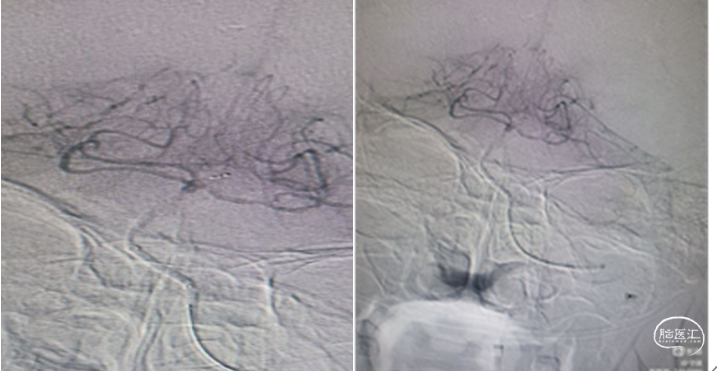

康复期间进行性加重,已超过了静脉溶栓治疗黄金时间,拟行血管内治疗机械再通。脑血管造影显示:基底动脉起始部闭塞,下图

血管内支架机械取栓:

更换8F动脉鞘,0.035in泥鳅导丝携带5F单弯造影导管和8F导引导管同轴到达左

侧椎动脉V1段起到通路和支撑作用。

释放取栓支架:

将6X30mm支架释放于基底动脉尖部与左侧大脑后动脉起始部。支架放置5分钟使支架充分展开,微造影可见基底动脉血流通畅。微造影可见基底动脉尖和双侧大脑后显影。

抽-拉结合取栓

1.裸支架导丝:缓慢拔出微导管于体外,最大限度增加中间导管管腔,有利于抽吸。

2、充分抽吸:跟进中间导管至基底动脉超始部,利用50mL自制负压卡口注射器连接中间导管进行负压抽吸。抽吸出黯红色血栓。

3.回拉支架:负压抽吸中间导管的同时,将取栓支架缓慢拉入中间导管撤出体外。

4.抽吸清理通路:接续二次抽吸中间导管直至血流通畅。

检查取栓结果:

抽吸除少了血栓,造影显示:基底动脉血流通畅。远端供血良好,双侧大脑后动脉供血良好。基底动脉中下段重度狭窄。